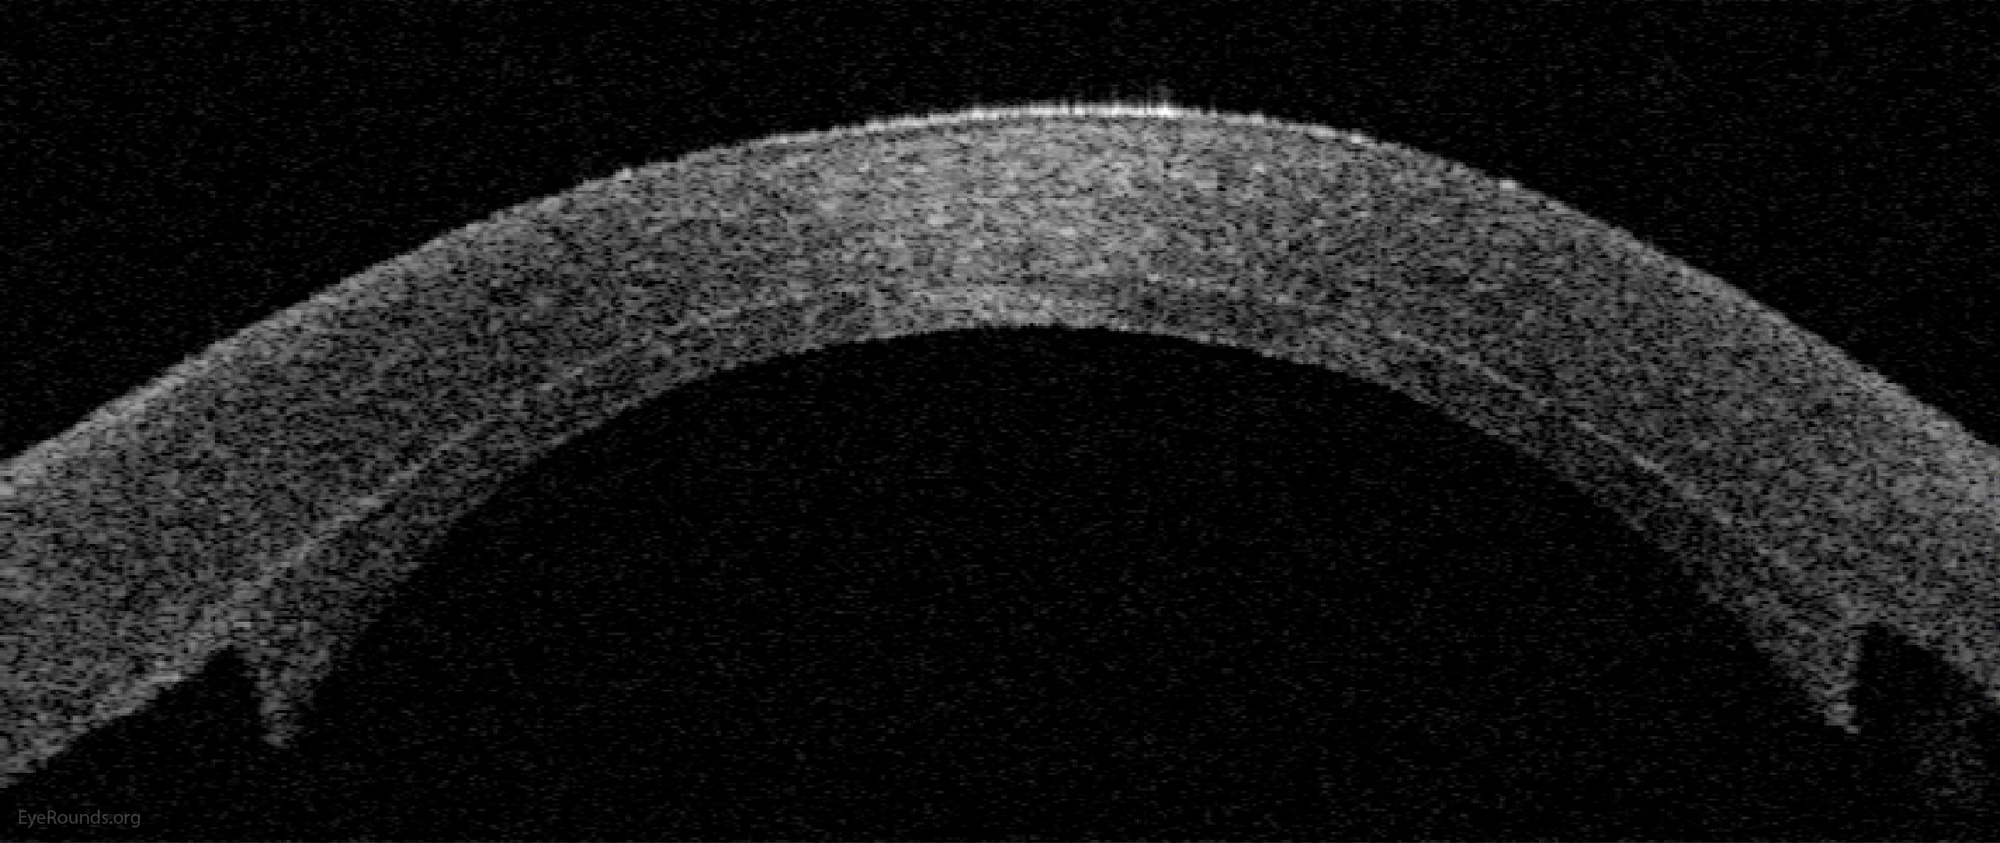

DMEK is a partial-thickness cornea transplant procedure that involves selective removal of the patient's Descemet membrane and endothelium, followed by transplantation of donor corneal endothelium and Descemet membrane without additional stromal tissue from the donor. The graft tissue is merely 10-15 microns thick. Similar to DSAEK, direct contact with the DMEK graft tissue should be avoided to prevent endothelial cell damage and graft failure. A clear corneal incision is created, the recipient endothelium and Descemet membrane are removed, and the graft is loaded into an inserter. After injecting the tissue into the anterior chamber, the surgeon orients and unscrolls the graft, and a bubble of 20% sulfur hexafluoride (SF6) is placed in the anterior chamber to support graft adherence (Figure 10). A variation known as Descemet membrane automated endothelial keratoplasty (DMAEK) utilized an automated preparation of the donor tissue that left a rim of donor stroma peripherally for easier tissue handling (Figure 11), but the procedure is no longer performed due to advances in DMEK that have allowed for easier insertion and manipulation of the graft tissue.

Because of thinness, fragility, and its characteristic scrolling properties (with the endothelium facing outward), the donor tissue can be difficult to handle and contribute to technical difficulties with the procedure. There is a higher risk of graft edge lifts (Figure 13) compared with DSAEK, sometimes requiring a re-bubble procedure.